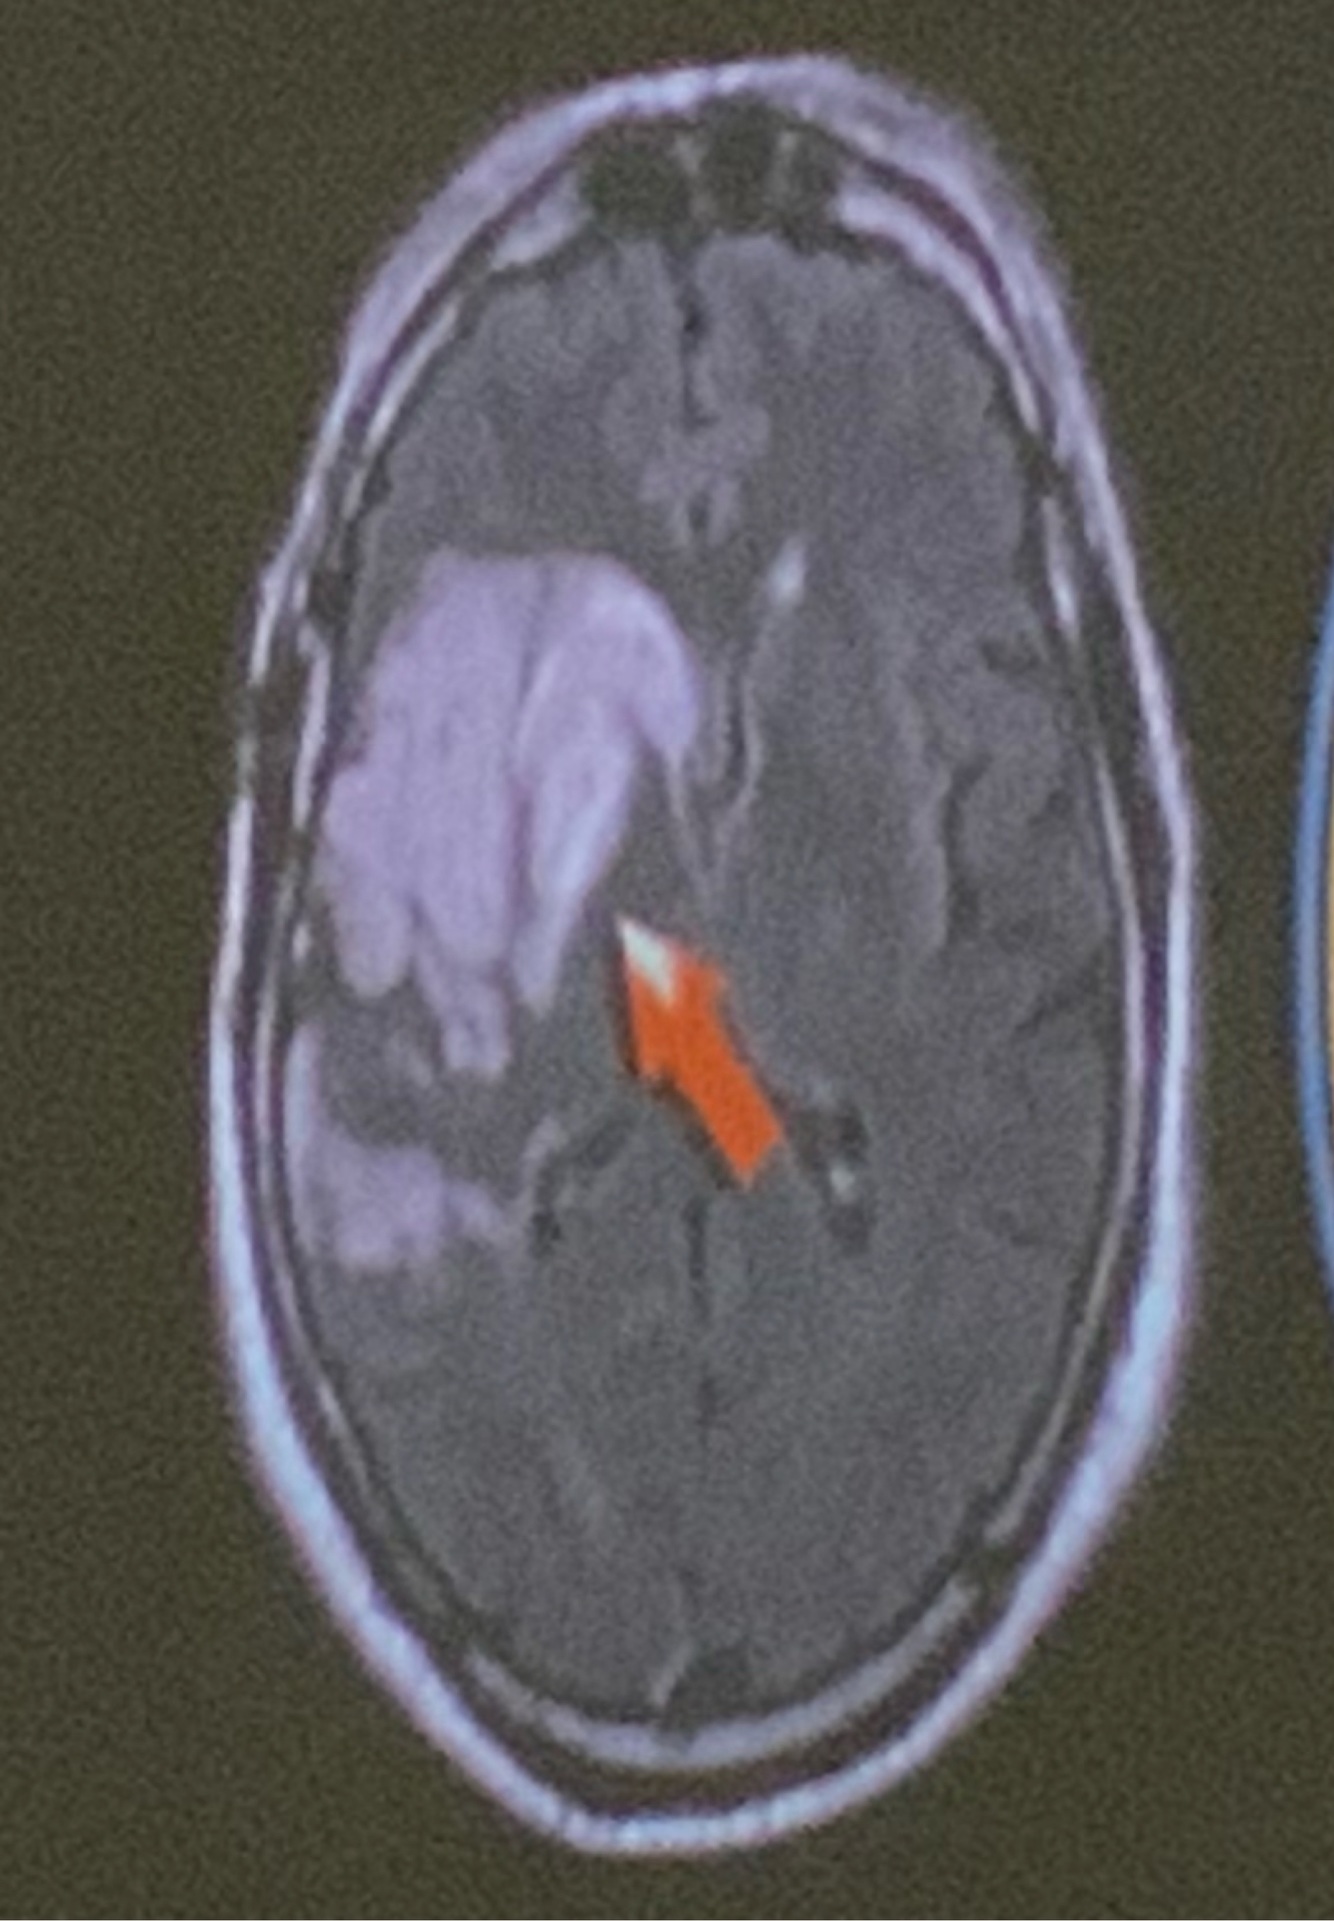

Q

Método de imagen utilizado y dx

A

Difusión, hemorragia de la acm